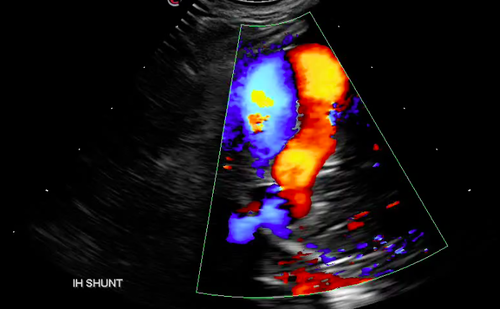

Mobile Imaging Veterinary Ultrasound (MiVU) is a mobile veterinary ultrasound service serving Richmond and the Hampton Roads area veterinarians.  MiVU conveniently offers advanced diagnostic ultrasound capability performed in your hospital thereby allowing you to preserve and maintain your doctor / client / patient relationship.  MiVU's goal is to provide services that are consistently prompt, accurate, and affordable. Services provided include but are not limited to abdominal ultrasound, echocardiogram with cardiologist interpretation, fine-needle biopsies, tru-cut biopsies, and cavity centesis.